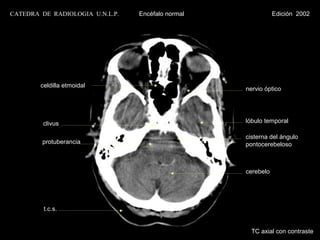

CATEDRA DE RADIOLOGIA U.N.L.P.   Encéfalo normal              Edición 2002

celdilla etmoidal

nervio óptico

clivus                                    lóbulo temporal

cisterna del ángulo

protuberancia                              pontocerebeloso

cerebelo

t.c.s.

TC axial con contraste